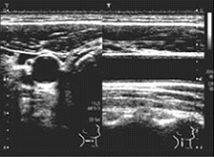

頸動脈エコー